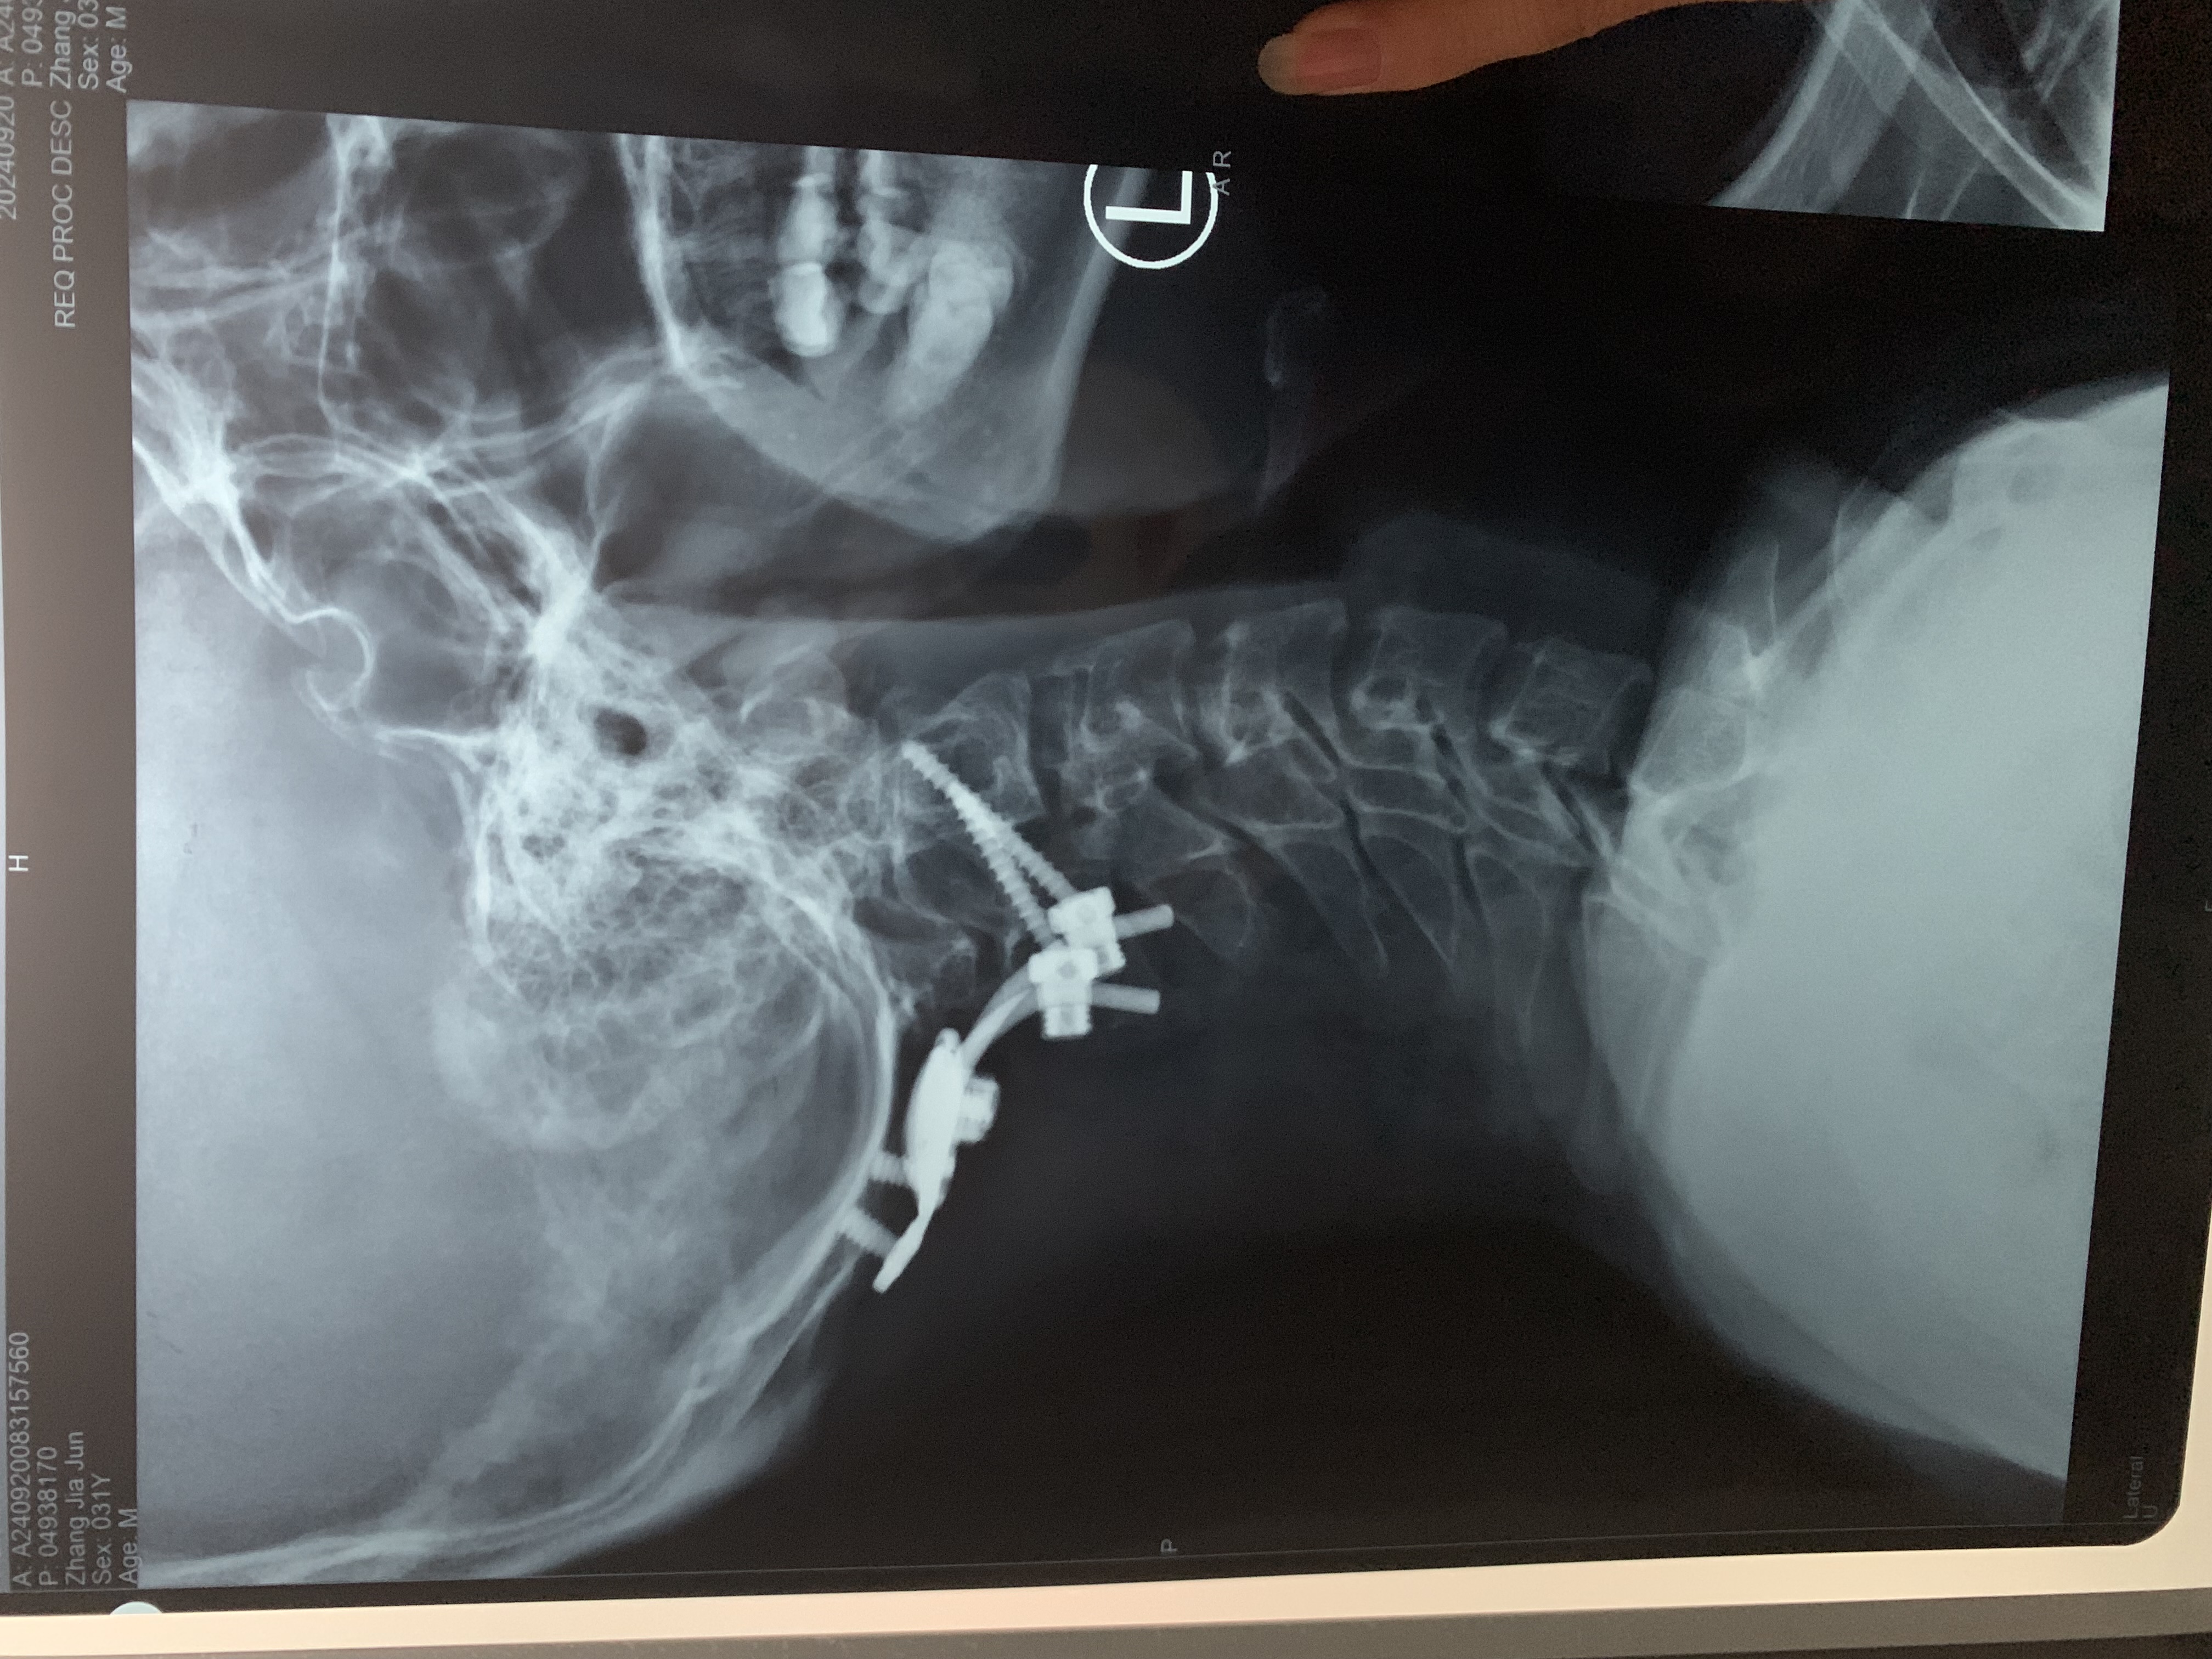

• 术后状况:头晕症状还在,但握拳有劲了,第二天看ct片子,寰齿间隙还是大于3mm,颅底凹陷没有任何改善。

• 术后影像:

• 2024.12.13,去北京拍片,当天走路有点多,感觉脑袋里面疼。影像报告脱位和颅底凹陷都还在,影像如下: